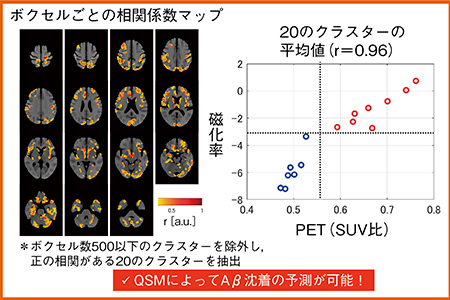

さらに,QSM+VBMと,脳へのAβ沈着を検出するアミロイドPETの比較を多施設共同臨床研究にて行っている。MCIまたはADの患者17名を対象とした解析では,QSM+VBMとアミロイドPETの患者間相関係数が0.3を超える14領域について,磁化率を平均化し,横軸にPET(SUV比),縦軸に磁化率をプロットした。Aβの陽性・陰性のカットオフ値にSUV比0.6を用いた場合,感度75%,特異度100%,正診率87%となった(図4)。

図4 QSMとアミロイドPETの比較

さらにボクセルごとに相関係数を求め,正の相関がある20のクラスターを抽出した。患者ごとの平均値をとり,磁化率(縦軸)とSUV比(横軸)をプロットすると,相関係数0.96と高い相関を示した(図5)。今後,検証が必要であるが,QSMによってAβ沈着の予測が可能であると考える。

図5 QSMとアミロイドPETの比較:ボクセルごとの解析結果